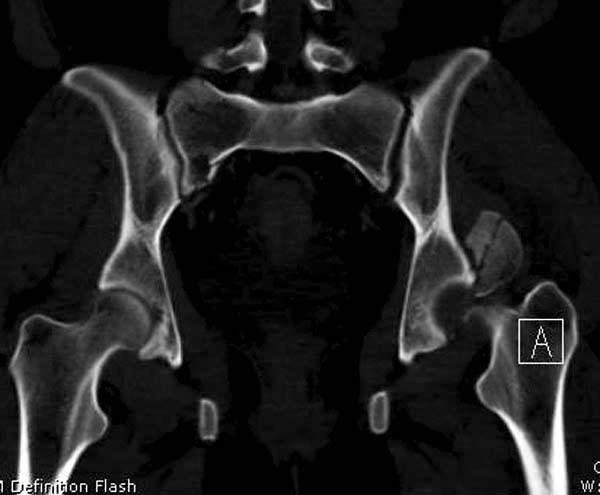

Женщина 28 лет, политравма.

По протоколу обследования больных с травмой сделаны все исследования и выставлен диагноз: разрыв печени и селезенки; множественные переломы ребер и лицевого черепа; стабильный перелом позвоночника, переломо-вывих головки левого бедра, перелом диафиза правого бедра, переломо-вывих правого тарана.

Вложение не в текстовом формате было извлечено&hellip;

Имя     : 8 CT3.JPG